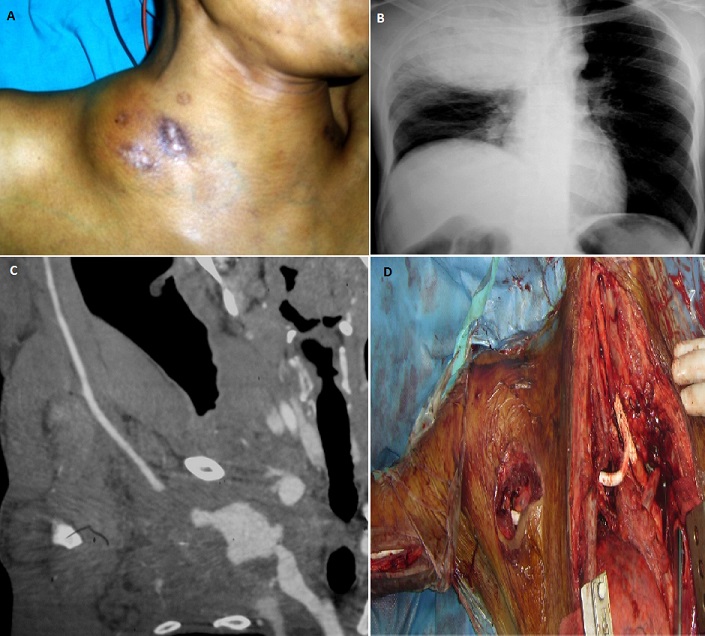

An infected false aneurysm of the subclavian artery in a 41-year old drug abuser

A 41-year-old man, with a history of intravenous drug abuse, presented with a mass in the right side of the neck. The mass had increased in size over a three-day period, producing local pain, hoarseness, shortness of breath, fever and pain of the right arm. Anamnesis told he performed internal jugular drug injection on a regular base. Physical examination revealed a pulsatile supraclavicular mass, with central necrotic lesions (A). Chest X-ray showed an opacity of the right hemithorax with left tracheal deviation (B). Additional computed tomographic angiography revealed a false aneurysm of the right subclavian artery, resulting in a filling defect of the axillary artery causing malperfusion (C). A midsternotomy with lateral extension was performed, which revealed an infected hematoma of a ruptured pseudo-aneurysm of the right subclavian artery. After ligation of the feeding vessels and debridement of the false aneurysm, an iatrogenic lesion of the branchio-cephalic trunk occurred, requiring interposition graft to the common carotid artery. Subsequently, a bypass graft from brachio-cephalic trunk to the humeral artery was performed (D). Postoperative course was complicated by an acute disseminated intravascular coagulation eventually leading to death An infected pseudoaneurysm of the subclavian artery as a consequence of intravenous drug use is extremely rare, with only 7 cases reported in the literature. It's a very grave entity, the risk of death is very important.